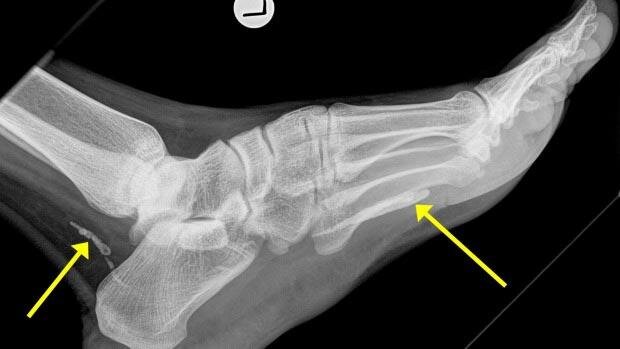

Неизвестный африканец иммигрировал в Австралию из Судана около 4 лет назад. Около года он жаловался на боль в ноге. Первоначально врачи думали, что это была инфекция, но на всякий случай решили сделать рентгеновский снимок больной ноги. И вот что врачи на нем увидели

Вместо инфекции, в ноге африканца находился червь-паразит, известный как дракункулёз, или ришта. Личинки этого червя могут проникнуть в организм вместе с питьевой водой. Скорее всего паразит попал в организм африканца ещё до его отъезда в Австралию. На данном снимке вы можете видеть червя, состоящего из двух частей, которые отмечены на снимке желтыми стрелками. Обычно ришта вырастают до определенных размеров, разрывают кожу и вылазят на поверхность, но этот парень решил умереть в организме носителя и ествественно стал разлагаться